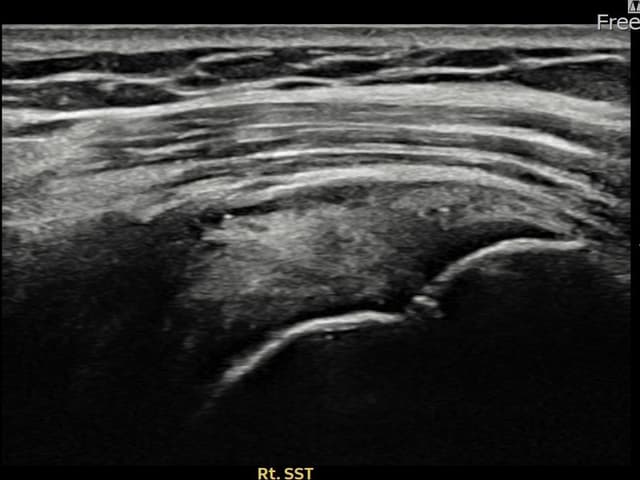

左侧 冈上肌腱 石灰化肌腱炎

9mm × 7mm